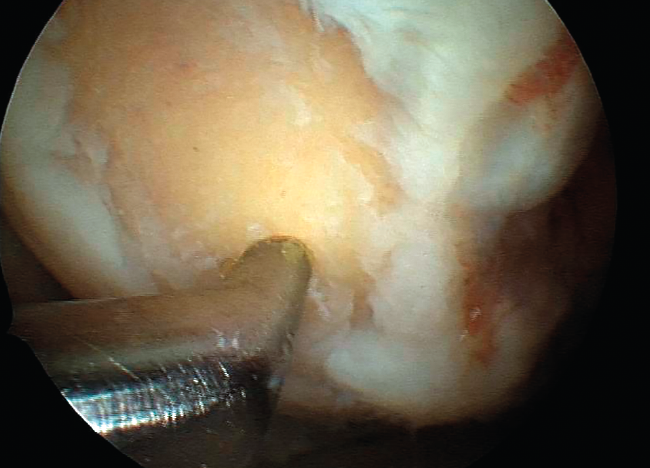

However, the microfractures technique in fact comprises a series of techniques grouped under the term of bone marrow stimulation (BMS). The techniques based on BMS have evolved over the years. Thus, the methodology has progressed from simple abrasion to large-calibre motorized perforations and non-motorized "ice pick" perforations (Figure 1), measuring between 1.5-2.5 mm in diameter, and finally to techniques that use small-calibre perforations with depths of up to 9 mm that are much less aggressive with the bone and marrow structure, and are referred to as subchondral drilling techniques.

Figure 1. Microfracture technique with a Steadman punch.